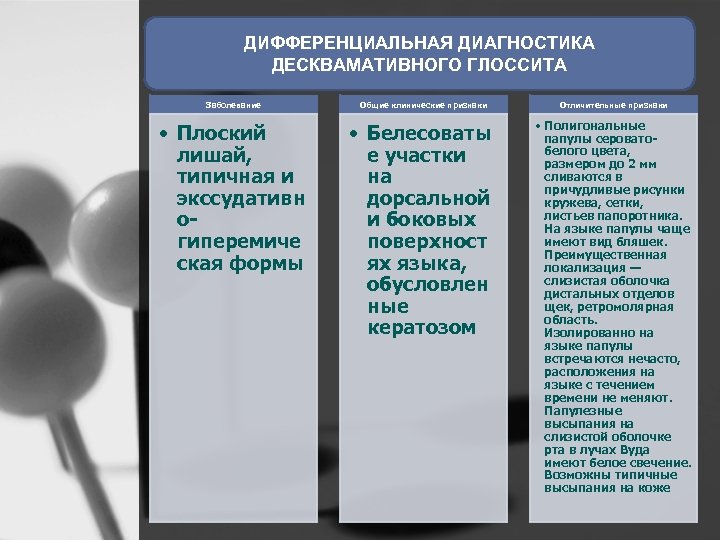

ДИФФЕРЕНЦИАЛЬНАЯ ДИАГНОСТИКА ДЕСКВАМАТИВНОГО ГЛОССИТА Заболевание • Плоский лишай, типичная и экссудативн о гиперемиче ская формы Общие клинические признаки • Белесоваты е участки на дорсальной и боковых поверхност ях языка, обусловлен ные кератозом Отличительные признаки • Полигональные папулы серовато белого цвета, размером до 2 мм сливаются в причудливые рисунки кружева, сетки, листьев папоротника. На языке папулы чаще имеют вид бляшек. Преимущественная локализация — слизистая оболочка дистальных отделов щек, ретромолярная область. Изолированно на языке папулы встречаются нечасто, расположения на языке с течением времени не меняют. Папулезные высыпания на слизистой оболочке рта в лучах Вуда имеют белое свечение. Возможны типичные высыпания на коже